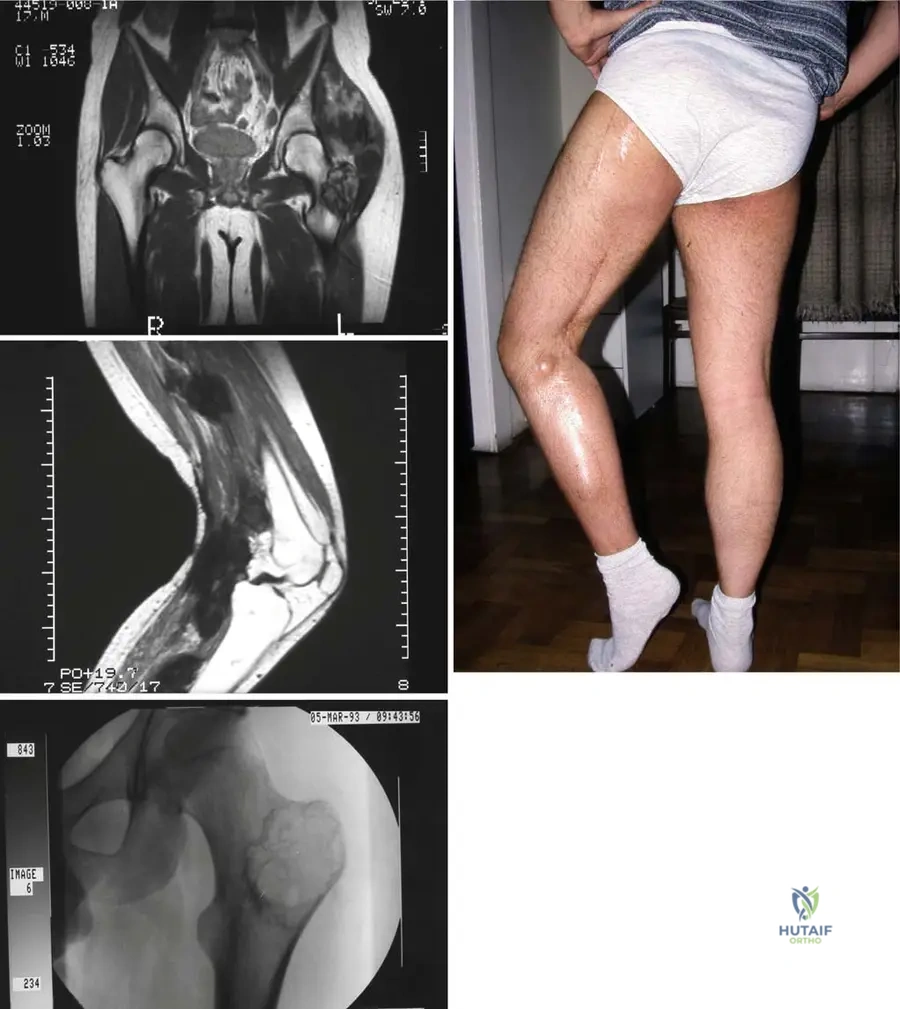

Question 12

View Answer & Explanation

Correct Answer: A

Rationale: The clinical context for Fig. 9.18 explicitly states: "Resected proximal fibula with adjacent liposarcoma." Main Distractor: B) Malignant fibrous histiocytoma (MFH). While MFH is a type of soft tissue sarcoma mentioned in the general text, the specific image context identifies the tumor as a liposarcoma.

A 63-year-old male presents with a deep-seated mass in his thigh. An MRI is performed to characterize the lesion. The axial T1-weighted image is shown.

Rationale: The clinical context for Fig. 9.19 states: "Axial T1(a) and axial T2-weighted MRI with fat saturation (b) showing typical MRI features of a soft tissue sarcoma with intermediate signal intensity on T1 (isointense with muscle)." Main Distractor: B) Markedly high signal intensity, brighter than fat. This is incorrect; T1 signal for STS is typically intermediate, isointense with muscle, not markedly high like fat.